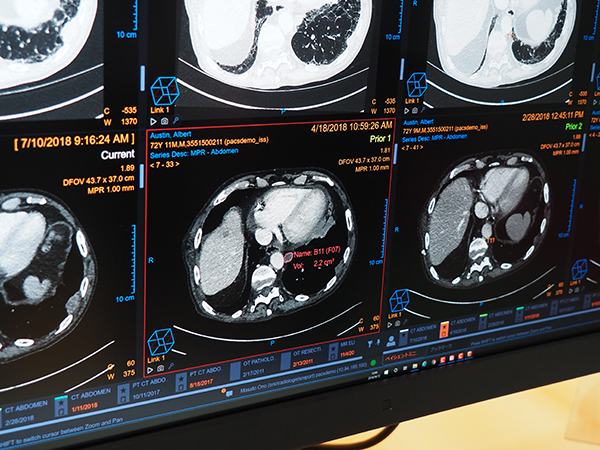

ITEM2019のトレンドともなったAIへの取り組みとしては,RSNA2018でも紹介したゼブラ・メディカル・ビジョン(ゼブラ社)のAIエンジンのVue PACSへの統合,自社開発の病変管理機能(Lesion Management)やCTの脊椎自動ラベリングなどを紹介した(すべてW.I.P.)。

ゼブラ社のAIは,Vue PACS Clientに統合されており端末で対象画像を表示すると,判断した結果を示すポップアップウィンドウが開く。部位や画像種別に応じて適応されたAIプロセスがアイコンで表示されるが,所見なしの場合はアイコンが緑,所見ありでは赤で表示される。マウスオーバーで判断内容の詳細が表示される。AIの判定結果はワンクリックでレポートに転送されるように,システムとしての連携が図られていることを説明した。ゼブラ社のAIエンジンはCT,一般撮影,マンモグラフィなどで10以上のプロセスが開発されているが,FDAの承認を受けているのは,“肺気腫”“脂肪肝”“冠動脈石灰化”“骨密度”“脊椎圧迫骨折”の5つである。そのほか,ケアストリームヘルスが自社開発しているAIは,胸部CT画像での肺結節をはじめとした,病変の自動認識・抽出,脊椎ラベリングの自動化などで,従来からVue PACSで提供してきた機能を自動化する方向で取り組んでいるのが特徴だ。

自社開発のAIによる胸部CT画像での肺結節の自動認識・抽出(W.I.P.)